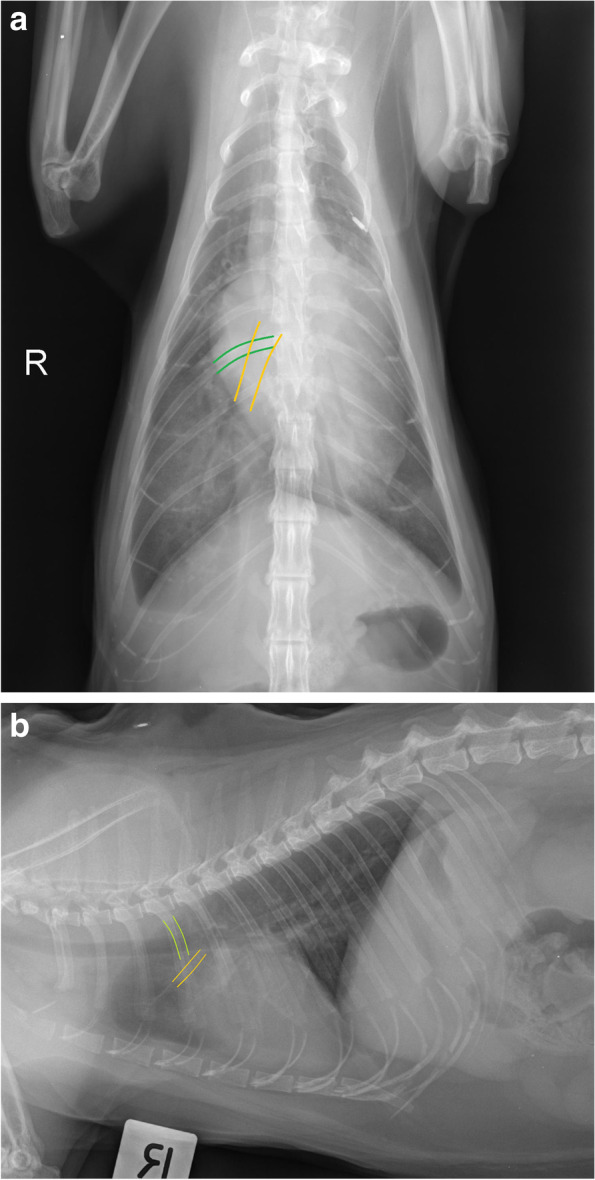

Fig. 3.

a VD projection. Caudal lobar vein (depicted by orange solid line) and veins at where they intersect with the 9th rib (depicted by green solid line) were considered enlarged if they were more than 1:1 ratio. This cat had bilateral enlarged caudal pulmonary veins and arteries with a scant volume of pleural effusion. b Lateral projection. Cranial lobar veins (depicted by orange solid line) were considered enlarged if it was more than 0.7 times the proximal third of the 4th rib (depicted by green solid line). This cat had enlarged cranial lobar veins and arteries, severely enlarged globoid cardiac silhouette with a scant volume of pleural effusion